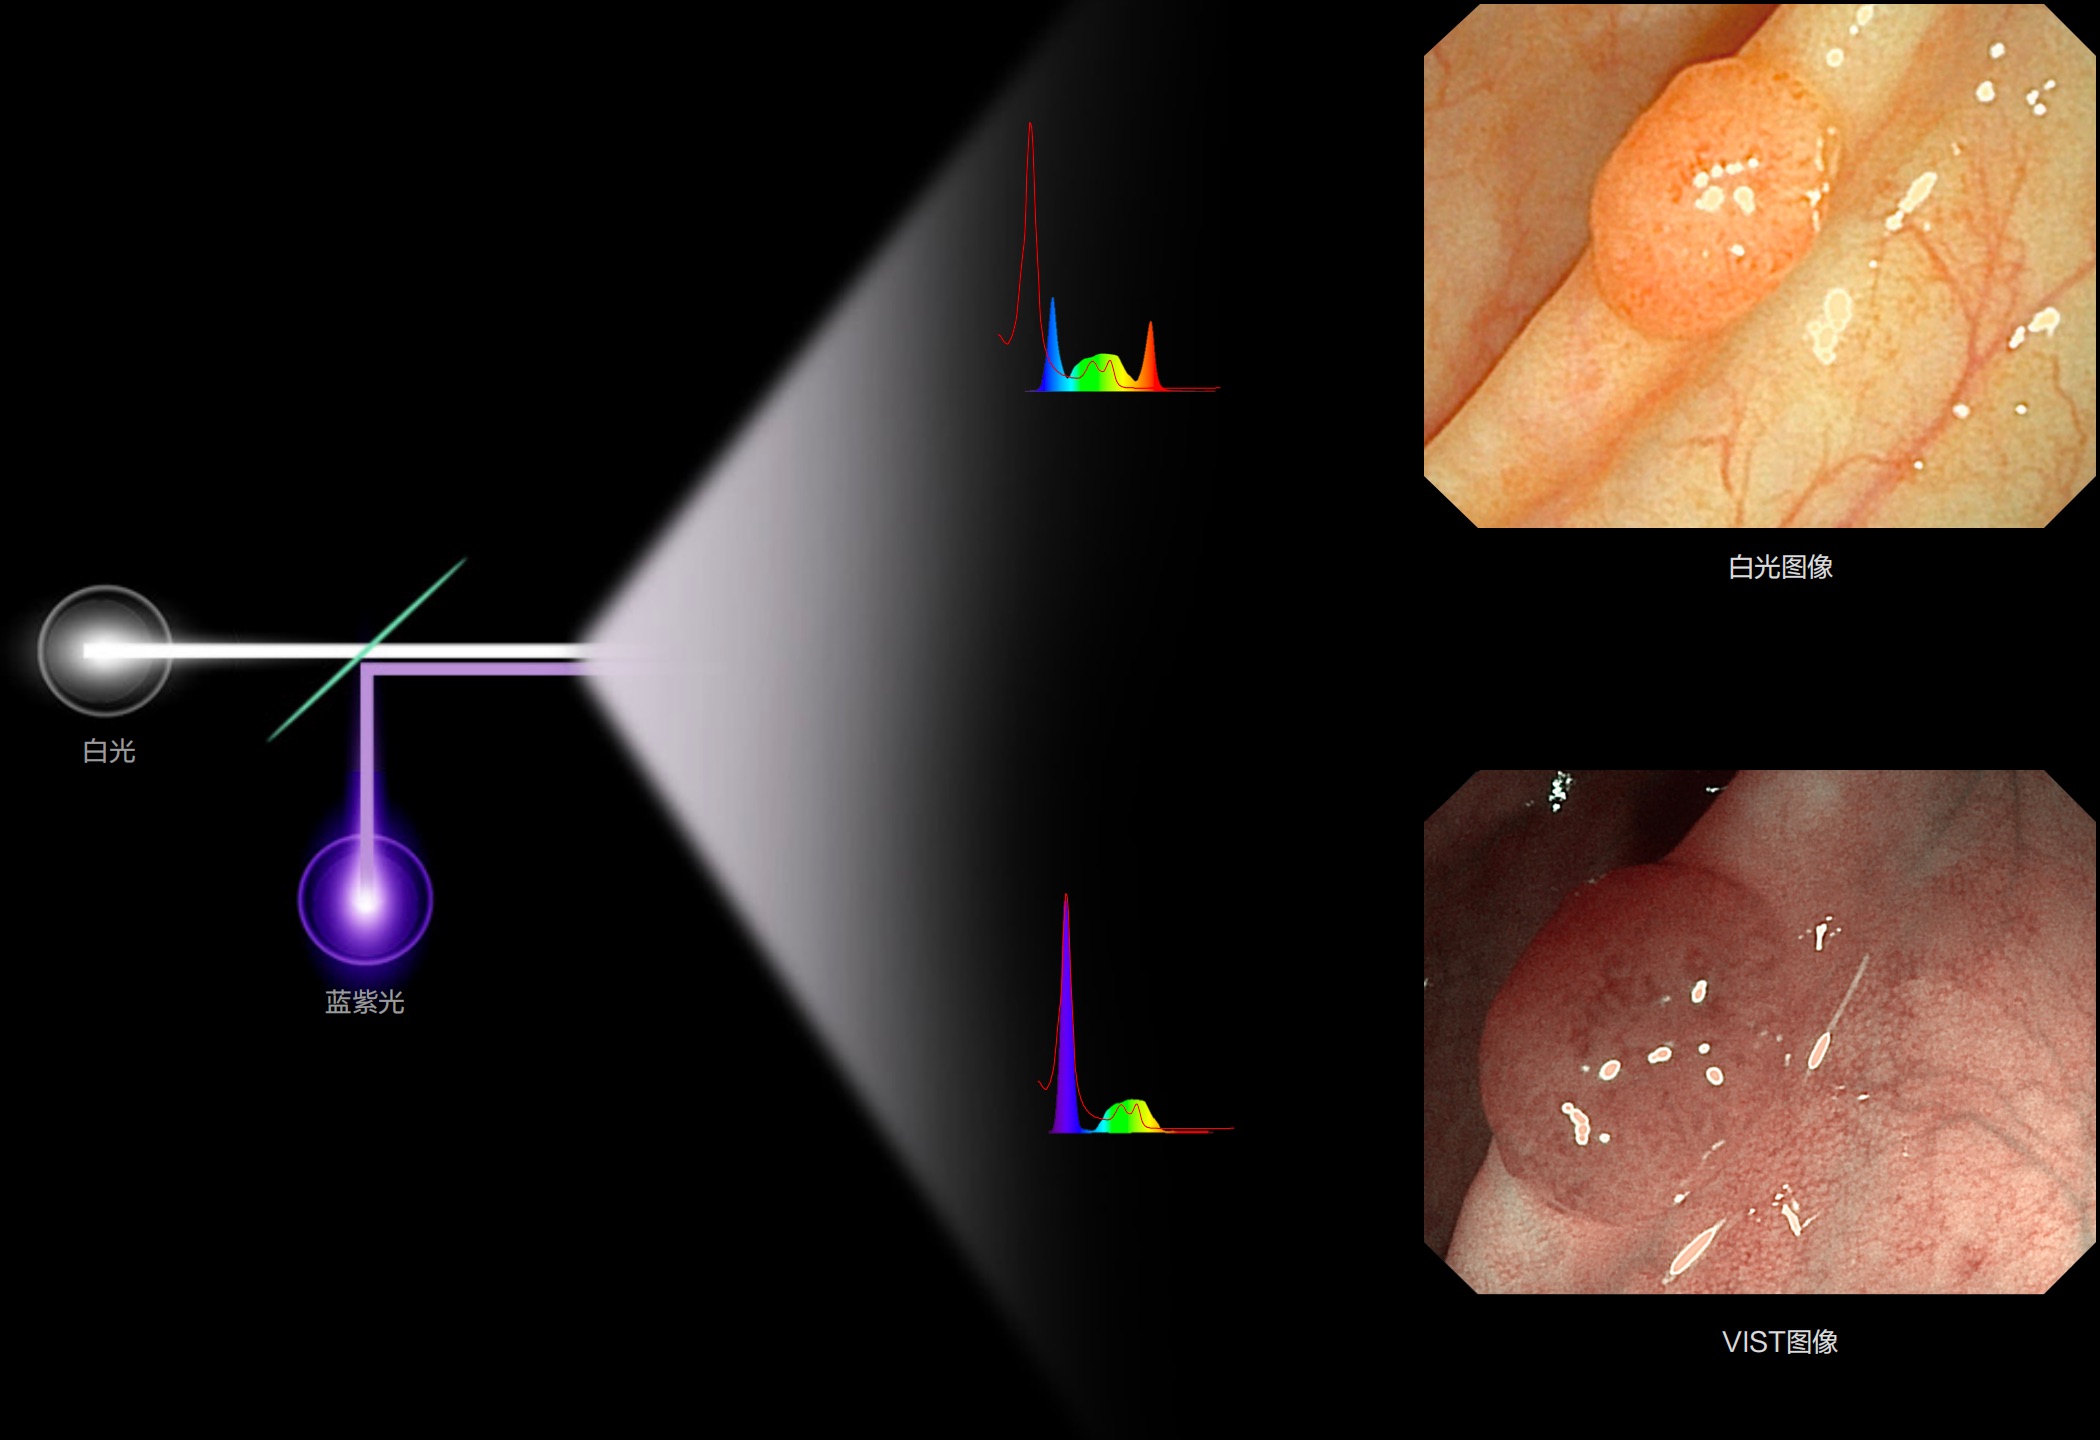

更高的光谱自由度,更长的光源使用寿命(平均使用寿命大于10,000小时),更低的功耗可减少科室运行成本。

(Spectral Focused lmaging, SFI)

能够凸显黏膜浅层和中层血管轮廓,适用于中、远景观察下的病灶识别和早癌筛查。

白光图像

白光图像

SFI图像

SFI图像

(Versatile Intelligent Staining Technology)

能够凸显黏膜浅层血管轮廓和黏膜表面微结构,适用于中、近景观察下的早癌精确诊断。